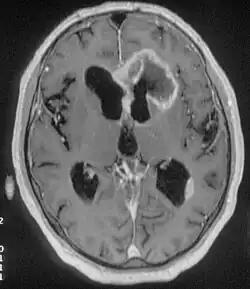

Tumor do lobo frontal esquerdo, multiocular, invasivo, com processo infiltrante.